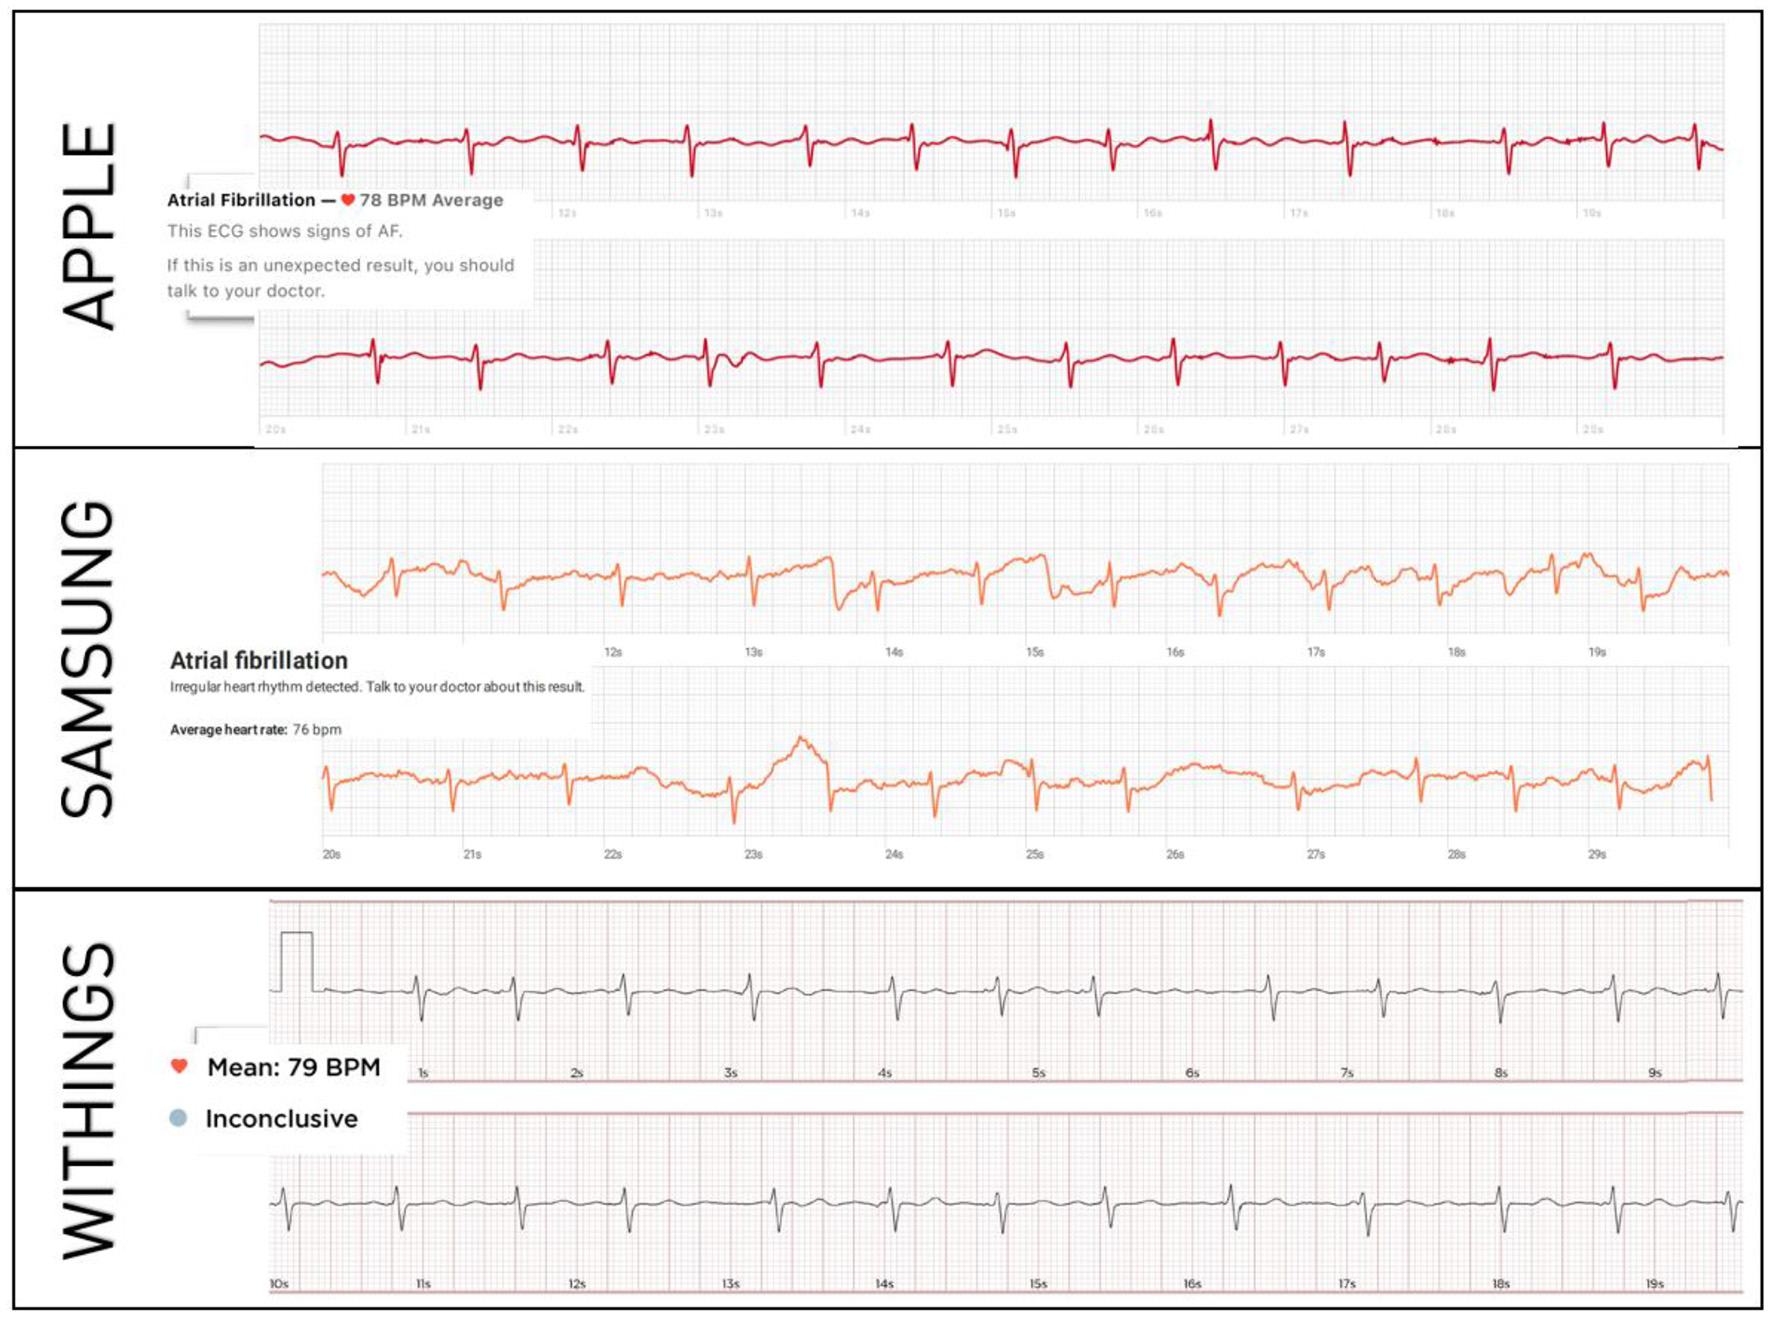

In total, 200 patients were enrolled (100 in SR, 100 in AF). Their mean age was 62 ± 7 years and 56% were male. Standard 12-lead and smartwatch ECGs from all the three models could be recorded in all patients, generating 200 12-lead ECGs and 600 single-lead smartwatch ECGs available for analysis. Representative examples of smartwatch ECGs from each model in a patient in AF is shown in Figure 1.

Figure 1

Representative examples of smartwatch ECGs in the same patient with confirmed AF. The diagnosis of AF is correctly made by each smartwatch's automated algorithm.